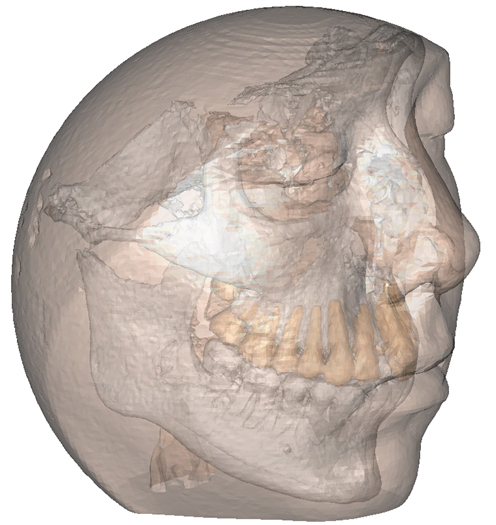

Το γεγονός αυτό σημαίνει: τρισδιάστατη ανασύνθεση, προσομοίωση και ανακατασκευή ανατομικών δομών, με σκοπό την ακριβή διάγνωση, τον προεγχειρητικό σχεδιασμό και την κατασκευή εξατομικευμένων εργαλείων και εμφυτευμάτων. Ή, ακόμα πιο απλά, ότι μια χειρουργική επέμβαση μπορεί να σχεδιαστεί και να αναπαρασταθεί με ακρίβεια χιλιοστού πάνω σε ένα ειδικά δημιουργημένο και διαμορφωμένο μοντέλο, με τα χαρακτηριστικά της συγκεκριμένης περιοχής, του συγκεκριμένου προβλήματος, του συγκεκριμένου ασθενούς. Ή, με όρους καθομιλουμένης, ασφαλέστερα, γρηγορότερα, αποτελεσματικότερα και οικονομικότερα για τον καθένα.

Η κατασκευή τρισδιάστατων μοντέλων κρανίου και γνάθων, δίνει, στη μεν ογκοχειρουργική, τη δυνατότητα για μεγαλύτερη ακρίβεια στις εκτομές και την αποκατάσταση των ελλειμμάτων, στη δε ορθογναθική χειρουργική τη δυνατότητα για μεγαλύτερη ακρίβεια του σχεδιασμού και της εκτέλεσης της χειρουργικής επέμβασης. Οι επεμβάσεις αυτές απαιτούν ακριβή προεγχειρητικό σχεδιασμό ανάλογα με την εντόπιση και το μέγεθος της βλάβης η της δυσμορφίας.

Στάδια Τρισδιάστατης Αποκατάστασης Κάτω Γνάθου: 3D απεικόνιση του ελλείμματος της γνάθου – 3D εικονική ανάπλαση της γνάθου – 3D εικονική προσομοίωση μικροχειρουργικής αποκατάστασης της γνάθου – 3D εκτύπωση

Ο σχεδιασμός γίνεται με βάση τα κλινικά και απεικονιστικά δεδομένα από την αξονική τομογραφία, αξονική αγγειογραφία και μαγνητική τομογραφία. Στην συνέχεια γίνεται η εικονική τρισδιάστατη ανασύσταση των απεικονιστικών δεδομένων και τρισδιάστατη μοντελοποίηση της γνάθου. Επιπλέον, αναπαράγονται τρισδιάστατοι οδηγοί κοπής της γνάθου, τρισδιάστατοι οδηγοί κοπής του αγγειούμενου οστικού κρημνού καθώς και ακριβής αναπαράσταση της συναρμογής των οδόντων με ανάδειξη της οδοντικής συγκλείσεως.

Ο τρισδιάστατος σχεδιασμός και η εκτύπωση μοντέλων επιτρέπει την προεγχειρητική διαμόρφωση των πλακών τιτανίου ώστε να εξοικονομείται χρόνος στην διαμόρφωση οστικών κρημνών και τη σταθερή οστεοσύνθεση των γνάθων στις διορθωτικές οστεοτομίες κατά την διάρκεια του χειρουργείου.